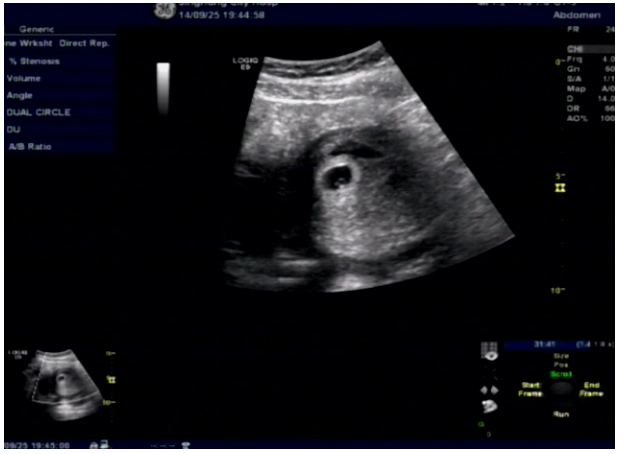

常规腹部及阴道超声:仪器:GE LOGIQ E9彩超:子宫形态大小正常,包膜完整, 实质回声不均匀,宫腔内可见一大小约:1.2*1.0cm的无回声。其内可见卵黄囊声像,未见胚芽组织及原始心管搏动,妊娠囊周围可见不规则的液性暗区。

双侧卵巢可见,于左侧卵巢旁可见一大小约:7.0*2.7cm混合回声,内见妊娠囊回声,大小约:1.0*1.0cm,其内可见卵黄囊声像,未见胚芽组织及原始心管搏动。

子宫直肠凹及膀胱直肠凹可见不规则的液性暗区,最深约:2.3cm。

超声影像采集图:

1.腹部超声图像

超声诊断:1.宫内早孕。2.左侧卵巢旁混合回声:提示异位妊娠(可见卵黄囊声像)。3.盆腔少量积血。